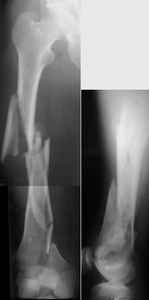

A new toy is more interesting and fashionable. And anyway it is not panacea, i have already seen presentations with LISS failures like the attached one presented by D.Seligson. And people also demonstrated incisions say that the method is not so LESS invasive as it supposed to be.

I presented a series of ~25 such cases at EuroTrauma'2004. Many cases were discussed here. I attach am example. Look also recent cases at http://www.hwbf.org/hwb/conf/alex58/scfx.htm,

http://www.hwbf.org/hwb/conf/alex63/alex63.htm